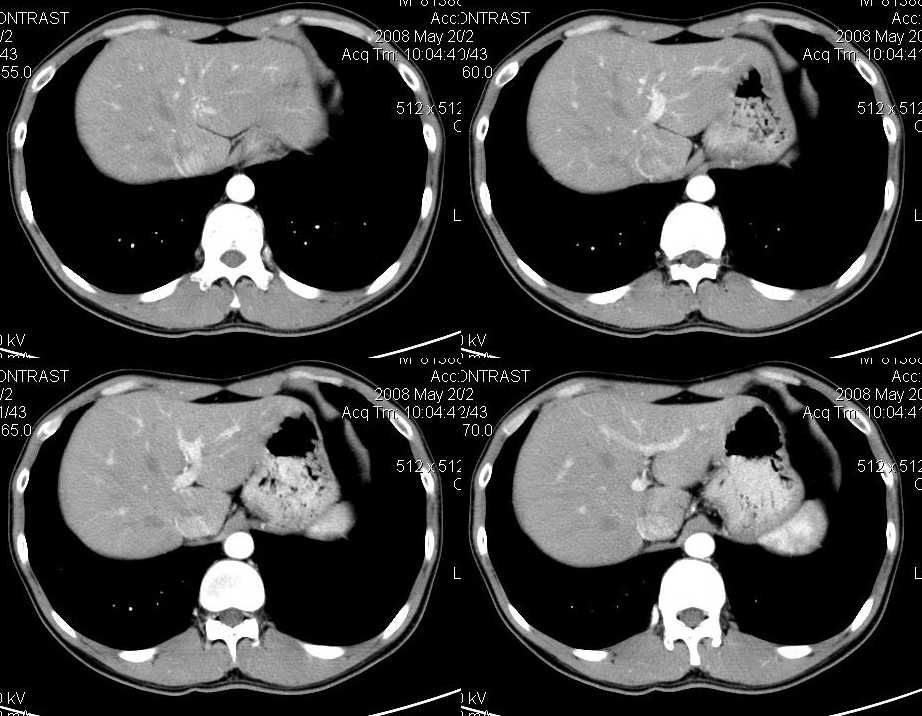

以下是引用liuyue在2008-6-7 15:28:00的发言:[br]典型的:肾癌。[br]动脉期强化明显,而静脉期密度明显降低,呈低密度。